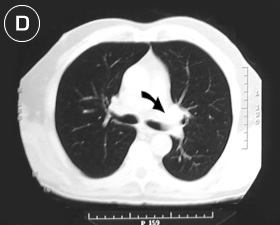

Corte Tomográfico "D"

nivel tercio medio del tórax.

hilear pulmonar

• Flecha Negra: Hileo pulmonar sin adenopatias. ventana aorto pulmonar de aspecto normal.

• Borde pleural normal, sin colecciones o derrame pleural.